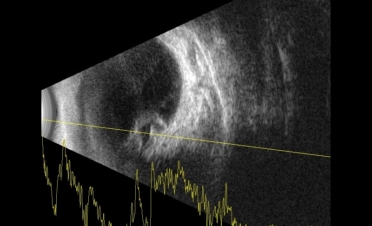

Se le realizó una ecografía y una retinografía para confirmar el diagnóstico.

La ecografía permite observar las estructuras del globo ocular cuando la transparencia de la córnea está comprometida o cuando deseamos observar con detalle los segmentos anterior y posterior del ojo.

En ambas pruebas se observaron imágenes compatibles con un desprendimiento de retina:

Imágenes de la ecografía de Fox, un perro de raza Pomerania con desprendimiento de retina en ambos ojos. Se descartaron otro tipo de lesiones oculares. Foto: IVO. (Clicar la fotografía para ampliar)